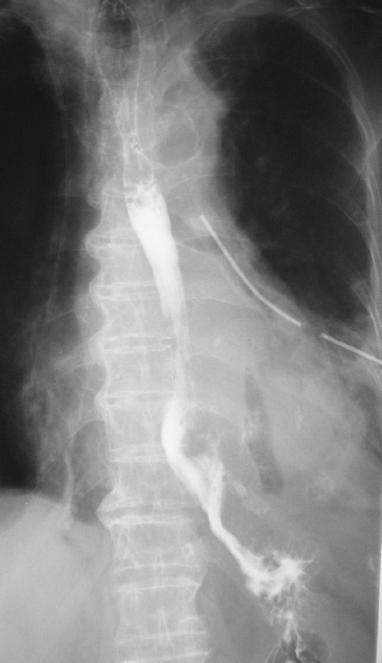

A chest tube was inserted under local anesthesia to drain the hydropneumothorax and the patient was submitted to a computed tomography (CT) scan of the chest and abdomen which also demonstrated the same findings of pneumomediastinum and hydropneumothorax and subcutaneous emphysema of the left hemithorax with no significant findings from the abdominal cavity (Fig. 1). A possible diagnosis of spontaneous esophageal rupture was considered which was confirmed with a gastrografin esophagography demonstrating a rupture in the left lower third of the esophagus (Fig. 2).

Figure 1 Gastrografin esophagography demonstrating a rupture in the left lower third of the esophagus and significant extravagation of gastrografin.